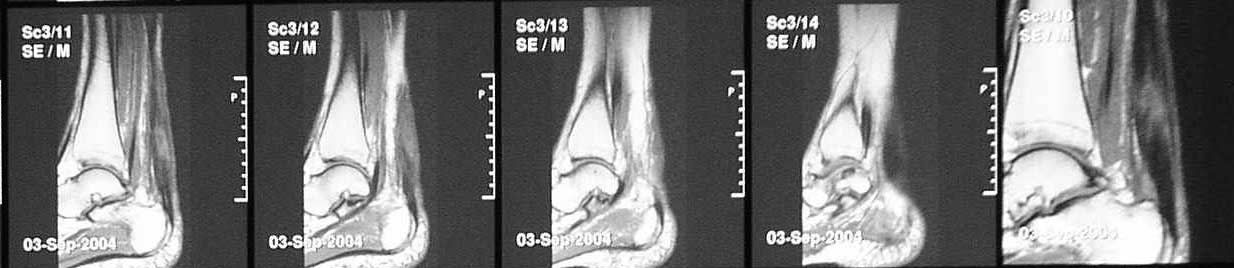

В сентябре сделана МРТ, цитирую заключение: "по внутренней поврехности сухожилия на уровне средней трети определяется очаг с неоднородной гиперинтенсивностью сигнала на T2W и изоинтенсивного сигнала T1W неправильной форму. Прротяженность очага до 43 мм в вертикальном диаметере. В центральной части очага на протяжении до 22 мм определяется прерыв и диастаз волокон ахиллова сухожилия. Заключение: Частичный дегенеративный разрыв ахиллова сухожилия, тендинит".

Что интересно, аналогичная МРТ-картина выявлена за месяц до операции. Однако в справке после операции ничего о разрыве нет.

Подобное решение основано на результате магнитно ядерного резонанса который показывает что разрыв сухожилия не превышает 50 процентов от общего диаметра